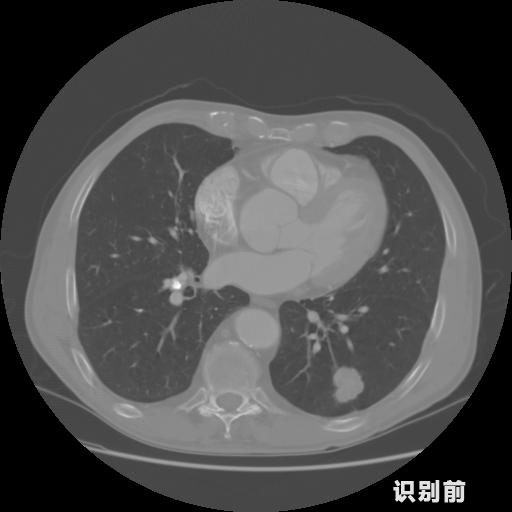

英特健康A(chǔ)I深度學(xué)習(xí)醫(yī)療圖像識(shí)別系統(tǒng)案例_胸部CT

03.jpg

報(bào)告:

1.發(fā)現(xiàn)肺結(jié)節(jié)的可能性為95.56%---位于框指數(shù)位置:[331.70554 366.13406 365.21707 403.96234]